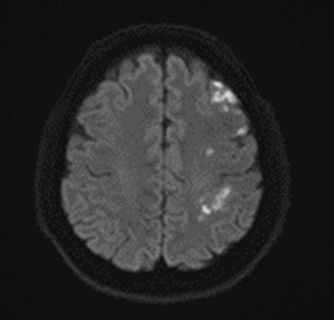

좌측 뇌에 급성 뇌졸중(뇌경색) 소견.

그림14.png

<Fig1.좌측 급성 뇌경색으로 진단된 뇌 mri 검사>

결론부터 말씀드리면, 급성 뇌경색은 MRI가 훨씬 정확합니다.

CT는 뇌출혈은 잘 보이는데, 초기 뇌경색은 안 보이는 경우가 많거든요.

실제로 이 환자분도 MRI를 찍었기 때문에

경색 부위를 명확하게 확인할 수 있었습니다.